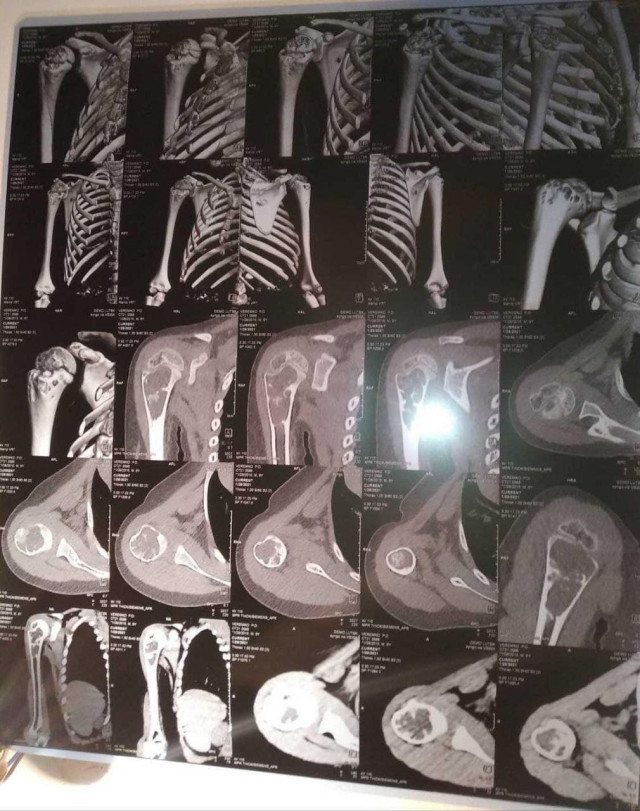

Шестирічному Павликові Веремку з прикордонного села Борового, що на Любомльщині (нині Ковельський район), встановили непростий діагноз – аневризмальна кісткова кіста правої плечової кістки, консолідований патологічний перелом правої плечової кістки. На хлопчика чекає складна операція із видалення частини ураженої кістки та довга реабілітація.

Обласні спеціалісти порекомендували спостерігатися й далі. А вже коли робили контрольні знімки, з’ясувалося, що пухлина почала збільшуватися. Дитині встановили інший діагноз – аневризмальна кісткова кіста.

Зараз ручка в дитини спухла й почала боліти. Пухлина збільшилася й тепер вона 2,5 на 2,7 см і має відростки по 4 мм.